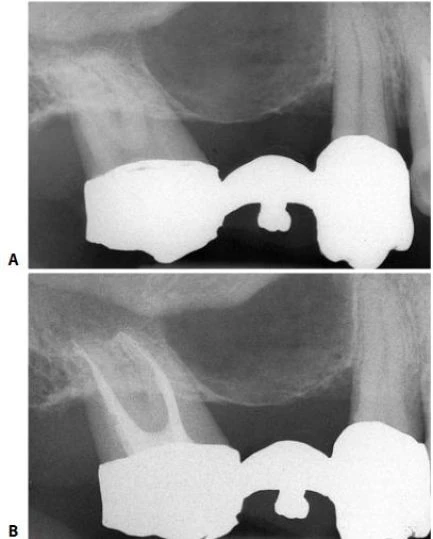

Hình 8.21. A.Phim sau điều trị của răng cửa bên hàm trên bên trái. Hình dạng và góc đọ của thấu quang, đường viền rõ và với kích cỡ của một nang. B. Sưng ở vùng khẩu cái. C. Hình ảnh mô học của tổn thương (×2,5). D. Phóng đại lớn, tổn thương mang những đặc trưng của u hạt (×250). E. Phim sau điều trị. Việc trám ngược được thực hiện ở răng cửa giữa bên phải. F. Một năm sau. Lưu ý rằng “sẹo quanh chóp” lớn vài mm phía trên chân răng cửa bên.

Hình 8.27. Phim Xquang trước điều trị của răng của bên hàm trên bên phải cho thấy hình ảnh tổn thương dạng nang lớn. Răng nanh và răng cối nhỏ đáp ứng dương tính với test thử tủy sống, trong khi đó răng cửa giữa cho kết quả âm tính. B. Một áp xe cấp tính lớn ở vùng xương ổ răng đã phát triển do một tổn thương mạn tính và nó thấy được ở vùng khẩu cái. C. Phim sau điều trị. D. Tám năm sau phẫu thuật cắt chóp. Do các triệu chứng sưng cấp tính tái diễn (có lẽ liên quan đến việc trám bít vùng chóp không đủ do gặp khó khăn khi làm khô ống tủy), cắt chóp và trám ngược bằng amalgam được thực hiện ở răng cửa giữa và răng cửa bên.